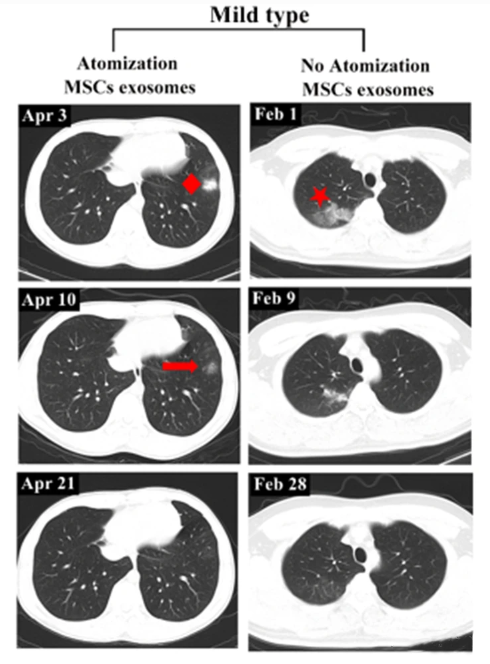

一轻度患者前后影像变化:

2020年4月3日,该患者第一次CT扫描显示左肺下叶外有孤立结节,4月4日,患者接受外泌体雾化治疗,4月10日,第二次CT检查显示左肺下叶结节密度明显降低,大小也缩小,4月21日,第三次CT检查,左下肺病灶完全吸收,从发现结节到完全吸收肺部病变所需的时间为18天。

相比之下,另一例患者(轻度病例,无雾化治疗)类似肺部病变的吸收时间为27天。

▲左:轻度病例,有雾化治疗

右:无外泌体雾化治疗的轻度病例